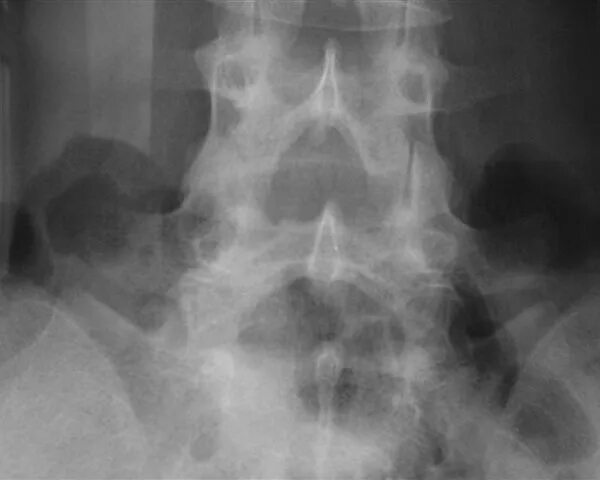

Анатомические и функциональные аномалии